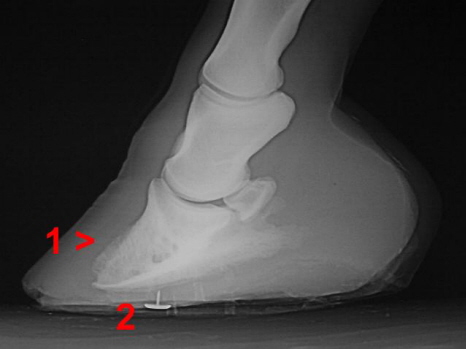

Hufrehe mit Hufbeinrotation